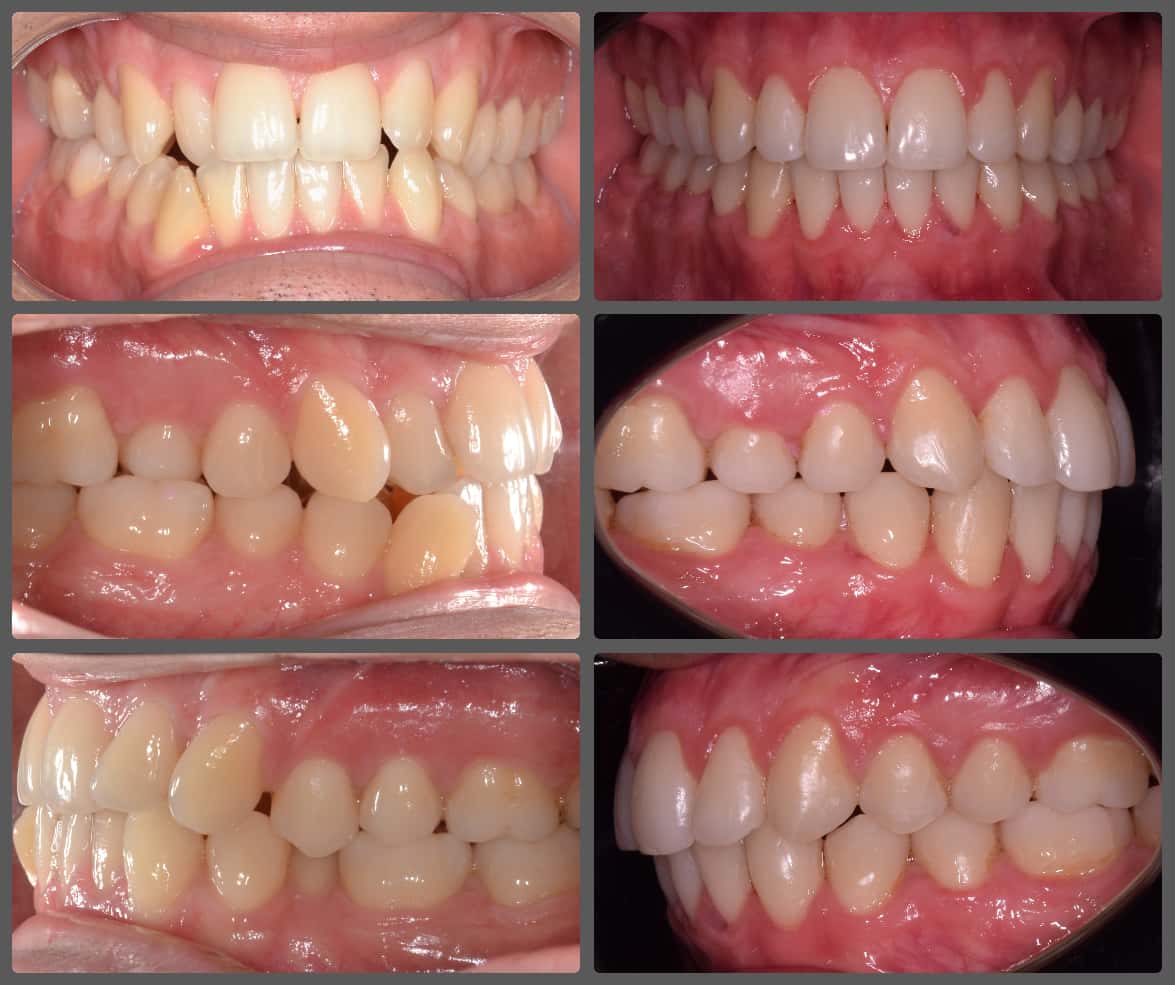

Bálint a 90 fokban elfordult jobb felső kismetszője miatt keresett meg engem. A vizsgálatokat követően kiderült, hogy a probléma ennél jóval komplexebb: súlyos keresztharapást, súlyos mélyharapást és felső rágósík billenést diagnosztizáltam nála. Alsó-felső H4 önligírozó fogszabályozó készülék, intermaxilláris gumihúzás és elülső harapásemelők segítségével korrigáltuk az eltéréseket. A bal oldali rágósík billenést fogszabályzási miniimplantátum alkalmazásával oldottuk meg. A bal felső-elülső fogakat felfelé mozgattuk, a miniimplantátumhoz húzva. Bálint esete igen komplex volt, ám kiváló együttműködésének köszönhetően 26 hónap alatt végeztünk a kezelésével (beleértve a 2-3 hónapos COVID-19 miatti leállást is). Az eredmény úgy gondolom magáért beszél!